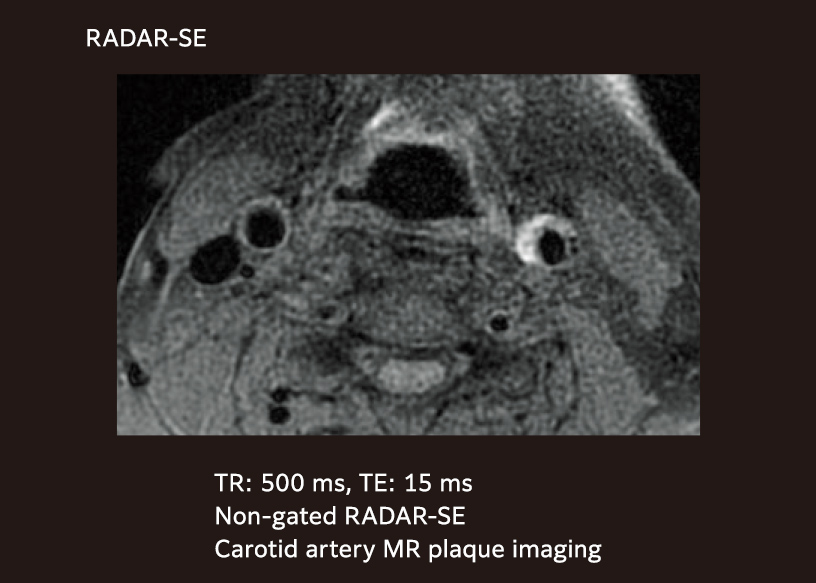

Diagnosis of plaque characterization

Diagnosis of carotid artery plaque characterization requires a high T1 contrast MR image.

The non-gated RADAR-SE method (also known as Radial Scan), maintains a constant TR without being affected by pulsation and can conduct scanning with a high T1 contrast appropriate for diagnosis of plaque characteristics.